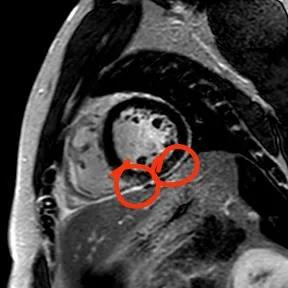

“快!做磁共振觀(guān)察心肌有無(wú)受損及程度。”影像診療中心陳寶瑩副主任為小燁進(jìn)行心臟磁共振平掃及增強(qiáng)掃描。結(jié)果提示:患者有急性心肌損傷,考慮心肌梗死。結(jié)果驗(yàn)證了小燁的心肌大片區(qū)失活。

方向比努力更重要,對(duì)于醫(yī)生而言更是如此,準(zhǔn)確把握病因方向,才能有效治療。心臟磁共振,成為非侵入性診斷心肌疾病的金標(biāo)準(zhǔn),能準(zhǔn)確地鑒別心肌炎、應(yīng)激性心肌病、心肌病淀粉樣變性、擴(kuò)張性心肌病及心肌梗死等,并能對(duì)心肌梗死后心肌纖維化進(jìn)行定量評(píng)估。